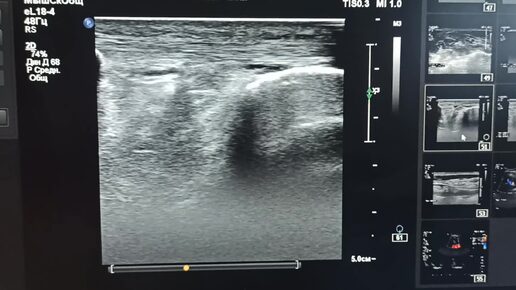

Узи: боль в колене.